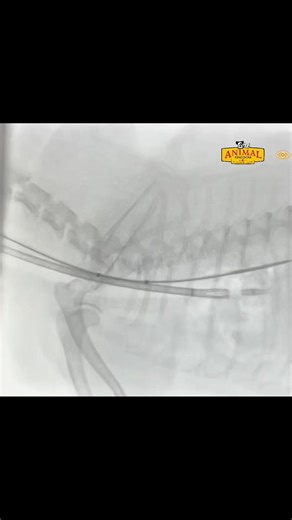

Stent Procedure - Collapsing Trachea Dog

Treatment